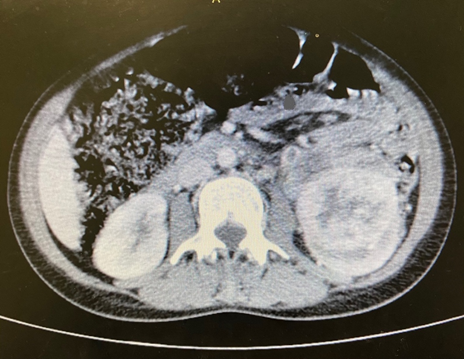

The abdominal image showed enlargement of the left kidney with a solid, expansive lesion that exhibited irregular contours and heterogeneous contrast enhancement, measuring 6.4cm along its longest axis, with involvement of the ureter and gonadal vein. In the pelvis, an extensive, expansive formation was identified in the bladder with a vegetative and infiltrative aspect, with uptake similar to that associated with renal injury and signs of invasion of the abdominal wall and pubic bones (Figures 1,2).

Figure 1 Computed tomography image of a massive solid lesion in the left kidney.